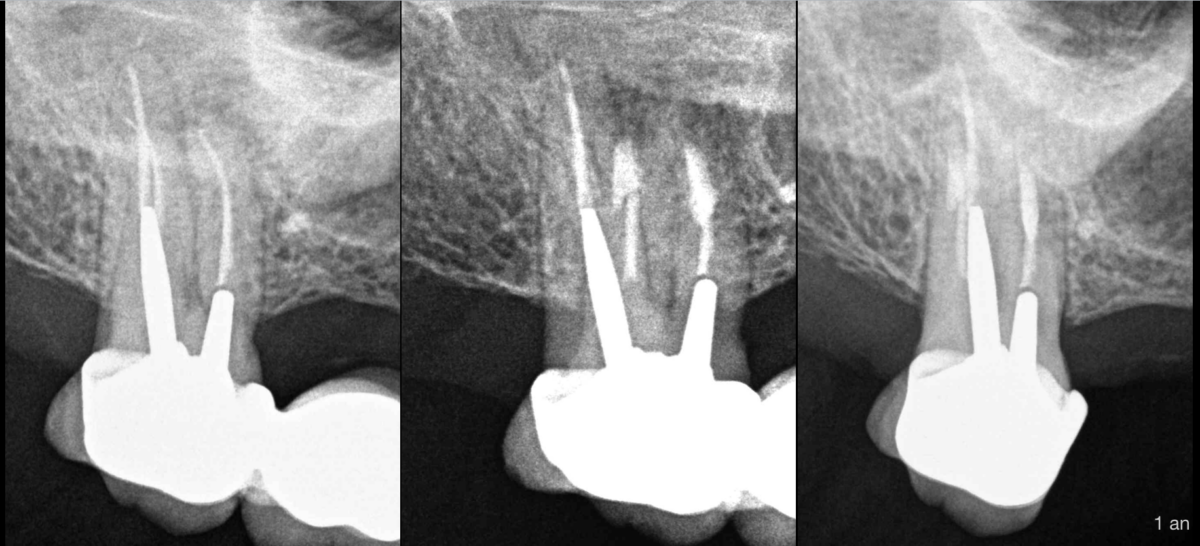

🔍 Microchirurgie endodontique dent des racines MV DV de cette 17.

Contrôle efficace à 1an.